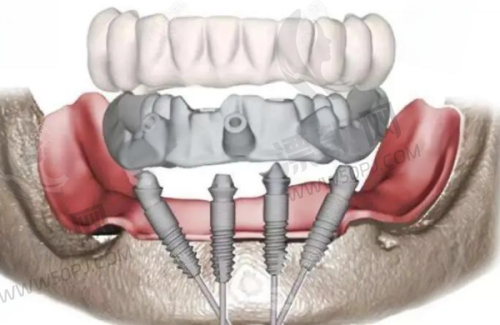

十、罗强口腔连锁种植院:懂你牙齿的城市种牙团队

这家口腔连锁在杭州多个区域设有分院,院长田宗从业十多年,曾进修于上海九院。机构主打精良数字导板进行种植诊断预判,尤其针对多年缺牙及顾虑术后调适的中年层客户建立专属治疗计划。 特色:术前数字模拟种植,全流程可视+追踪。 适合人群:错过黄金修复期、需高质量长期方案者。